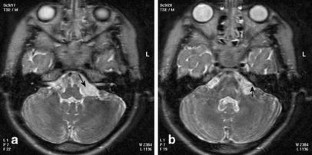

Facial nerve palsy in posterior fossa arachnoid cysts: report of two cases

Two patients with a posterior fossa arachnoid cyst responsible for isolated facial nerve palsy are reported.

The relationships between the cyst and the facial nerve and between the facial nerve palsy and the size variation of the cyst are discussed and documented by pre- and postoperative magnetic resonance imaging.

Fig. 1